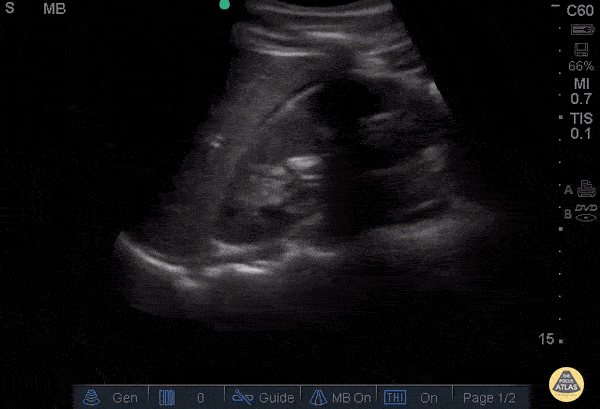

Objectif

Évaluation des cas de dyspnée, d'infection pulmonaire ou d'insuffisance cardiaque.

Points clés

- Repérage du diaphragme et de la ligne pleurale.

- Identification du signe de la "marche d'escalier" ou de la colonne vertébrale visible (liquide).

- Différenciation entre un épanchement liquidien et une condensation pulmonaire.

- À ne pas confondre avec : ascite sous-diaphragmatique.